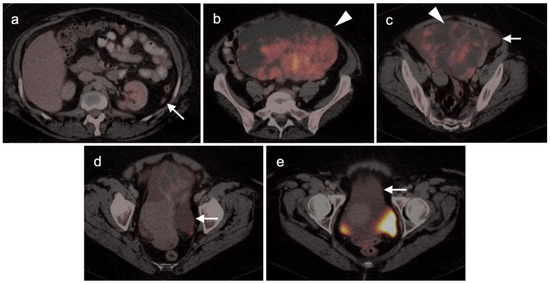

2.2. Ovarian Epithelial, Fallopian Tube and Primary Peritoneal Carcinoma

2.3. Uterine Neoplasms: Endometrial Carcinoma, Uterine Sarcoma and Leiomyoma

2.3.1. Endometrial Carcinoma

2.3.2. Uterine Sarcoma

2.4. Cervical Cancer